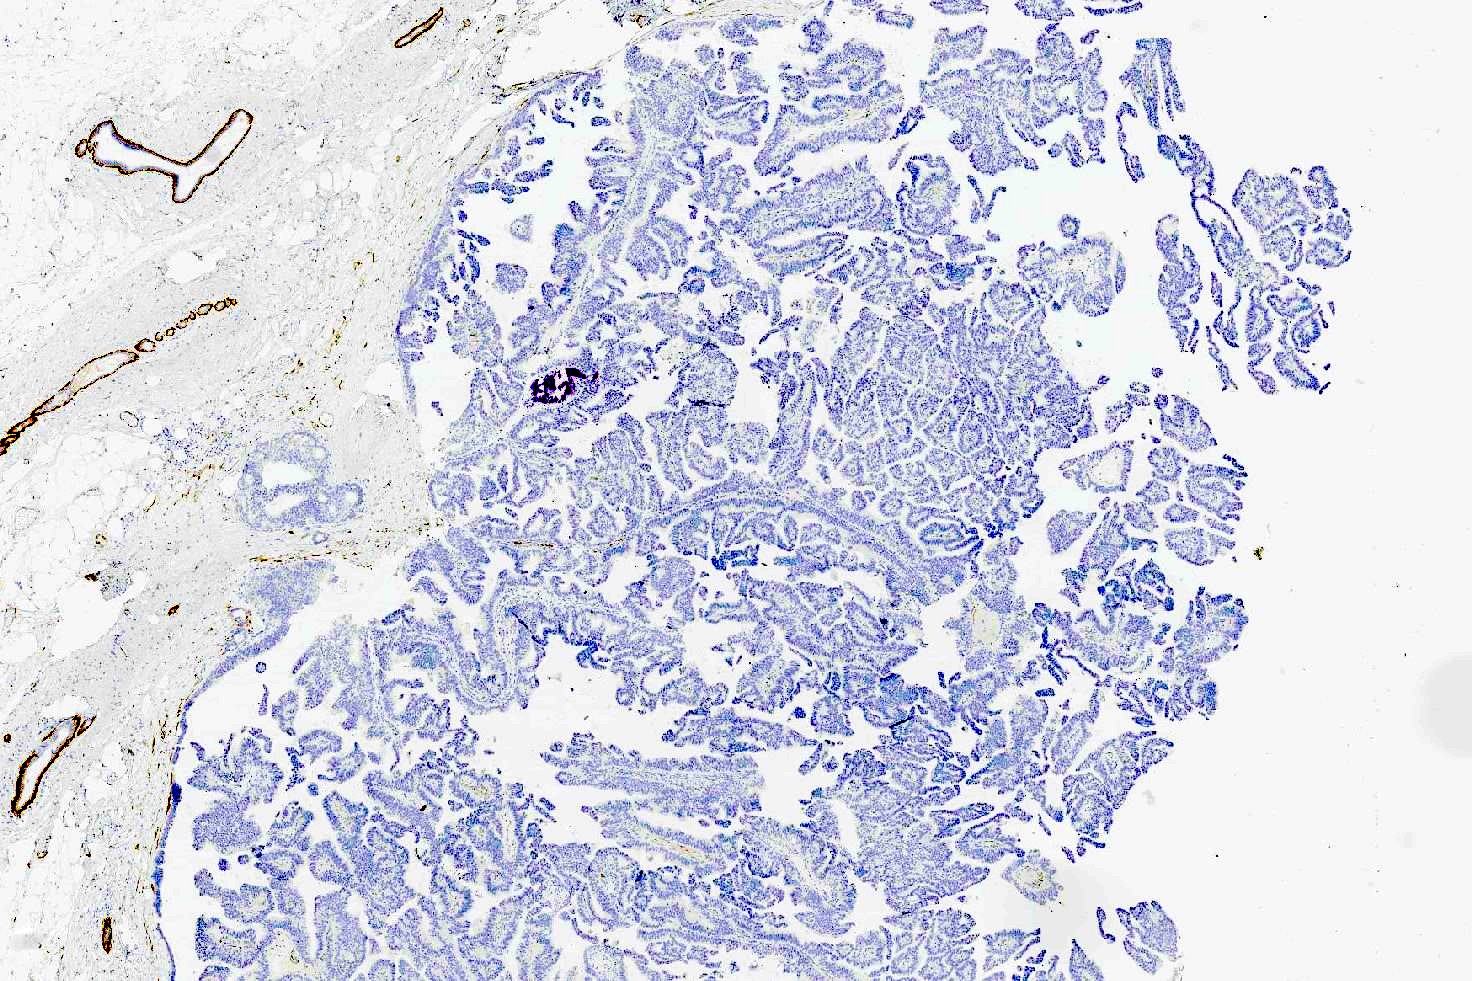

- Most show complete lack of myoepithelial cells along the papillae and around the periphery of the tumor (Am J Surg Pathol 2006;30:1002, Am J Surg Pathol 2011;35:1)

Negative stains

- Myoepithelial markers (i.e., p63, calponin, actin, smooth muscle myosin heavy chain, CD10) negative within papillae and around the tumor or focally present at the periphery of the lesion (Am J Surg Pathol 2006;30:1002, Am J Surg Pathol 2011;35:1, Curr Probl Cancer 2018;42:291)

Microscopic (histologic) images

Contributed by Kristen E. Muller, D.O. , Mariel Molina Nunez, M.D. and Julie Jorns, M.D. (Case #518)